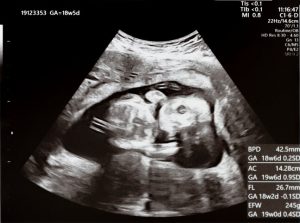

Forscher der University of Cambridge haben in einer großen neuroimaging-Studie untersucht, wie das menschliche Gehirn von Mitte der Schwangerschaft bis kurz nach der Geburt wächst und sich strukturell verändert. Dafür nutzten sie eine riesige Bilddatenbank – teil des Developing Human Connectome Projects – mit fast 800 fetalen und neugeborenen MRT-Scans. Diese Daten erlaubten es ihnen, die Entwicklung nicht nur punktuell, sondern als kontinuierlichen Prozess zu verfolgen.

Wichtig ist: Die Studie verknüpft pränatale (vor der Geburt) und postnatale (nach der Geburt) Daten, sodass erstmals exakt bestimmt werden konnte, wann Unterschiede im Gehirn sichtbar werden. Was sie fanden, ist überzeugend: Bereits ab der Mitte der Schwangerschaft, lange bevor äußere Umwelteinflüsse (wie Erziehung, Spielverhalten oder gesellschaftliche Rollen) eine Rolle spielen, zeigen sich messbare Unterschiede in der Entwicklung männlicher und weiblicher Gehirne. Dabei geht es nicht um einfache Klischees über Denk- oder Verhaltensweisen, sondern um Messgrößen im Hirnwachstum: